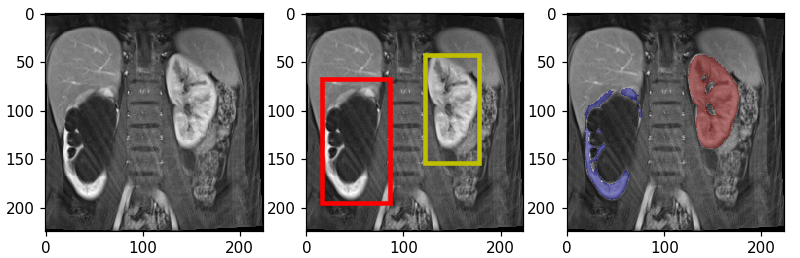

To optimize the parameters of the proposed framework for automated segmentation of normal and abnormal kidneys, we performed cross validation experiments on 24 subjects (10 with normal and 14 with abnormal kidneys). We used precision, recall, dice coefficient (DSC) or F1-score and volumetric estimation error (VEE) for evaluating the algorithm segmentation performance. F1-score, which is the harmonic average of precision and recall, reports the accuracy of the overlap between the predicted and true manual segmentation. We also report the performance of the model, trained using 24 subjects, and tested on 12 kidneys from 6 previously unseen subjects (3 patients with normal and 3 patients with pathological kidneys) that were not included in the training process. As explained in section 3, we train each of the localization and the segmentation networks independently using the training data and the manual segmentation masks. Segmentation results are shown in Figure 2 for one normal and one abnormal kidney example from the test set. Middle figure in each row is showing the result of bounding box detection. Predicted output consisted of three classes; right kidney, left kidney and background. After extracting three classes from initial segmentation masks and forming the bounding boxes, each class was scaled to volumes and the original time dimension was resampled, interpolated and added to the data as the channel information. Finally, the segmentation classifies each voxel in the high resolution image into kidney or non-kidney class. Third figure in each row is showing the result of segmentation and re-positioning each kidney back into the detected bounding box. The resulted average performance measures for final unseen test cases are reported in Table. 1. Mean F1-scores for three patients with normal and three with abnormal kidneys were and respectively.

(b) Abnormal Kidney (F1-score: 88.27 )